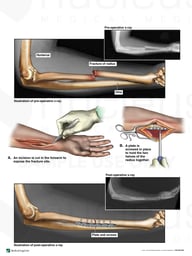

ACL Reconstruction Surgery

Image

exh46142b-nl